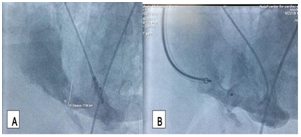

A 68 years old female patient who is a known case of hypertension and dyslipidemia presented to the emergency department with typical ischemic chest pain and electrocardiographic findings of anteroseptal STEMI. Patient received thrombolytic therapy and consequently had coronary angiography and then refered to our hospital, 15days post infarction for further management. Transthoracic echocardiography revealed moderate left ventricular dysfunction, EF 40%, anteroseptal and apical akinesia, small apical aneurysm, large VSR (17'14mm) with dominant left to right shunt and right ventricular systolic pressure of 45mmHg. An informed consent was obtained and the patient prepared for elective cardiac catheterization with intending of transcatheter closure of the VSR. Under local anesthesia and transthoracic echocardiographic guidance , right femoral and internal jugular vascular access was obtained and selective left coronary artery and left ventricle (LAO/Cranial 35/35) angiography was performed (Figure 1).

Figure 1 Transthoracic echocardiographic four chambers view shows the apical ventricular septa! defect with left to right shunt.